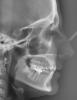

Layla Опубликовано 27 сентября, 2012 Поделиться Опубликовано 27 сентября, 2012 (изменено) Добрый день! Очень нужна консультация специалистов, т.к. я в полной растерянности. Так сложились обстоятельства, что процесс исправления прикуса я начала в другой стране и достаточно спонтанно.Мне 26, 5 лет. Была на консультации у 3 докторов, 2-ое из которых, не гляди на снимки с ходу сказали, что нужен аппарат RPE (в моем случае, как я поняла по фото, Хайрекс). 1 доктор советовал удалять. О хирургическом расширении никто из 3 не говорил.За 2 недели сделали аппарат и поставили почти 2 недели назад. Врач ничего толком не объяснила, ни планы лечения, ни возможные последствия, только сказала, что через пару дней я об аппарате забуду и что нужно раскручивать 3 раза в неделю.Я спросила, на сколько нужно расширить челюсть, она ответила -10 мм. Первые дни была сильная боль в области шестерок, на которых стоят кольца, жевать вообще не могла, да и до сих пор с трудом, челюсть не смыкается. Весь язык в ранах и не заживает , полоскания и сосательные таблетки от стоматита не помагают, слева верхние дуги врезаются в небо. результат -4 кг за неделю.Дикция ужасная, работа предполагает лекции на большие аудитории, не знаю , что делать. Пришлось самой начать изучать все в интернете.в итоге возникли вопросы по поводу адекватности лечения.Уважаемые специалисты, пожалуйста, посмотрите снимки , может вы сможете что-то порекомендовать.1. Нормально ли, что не попросили удалить 8-ки, хотя на нижней челюсти они в ужасном положении?2. Есть ли вероятность, что небный шов не разойдется и что делать в данном случае ? за почти 2 недели чувствую небольшое напряжение в переносице ( вроде как-то врач говорил, что искривлена) , щель между 1-ками не появляется.3. Какие могут быть негативные последствия расширения в моем возрасте?4. Можно ли в моем случае обойтись без удаления?5. Можно ли исправить прикус без хайрекса в моем случае или заменить его на что-то другое?6. Что делать с израненным языком, т.к. принимать пищу вообще не представляется возможным.7. И самое главное, как звучит мой диагноз?Родители просят название, а врач не сказала...Заранее огромное спасибо, очень жду ваших ответов и советов. Изменено 27 сентября, 2012 пользователем Layla Ссылка на комментарий

Force Опубликовано 30 сентября, 2012 Поделиться Опубликовано 30 сентября, 2012 34-36 - нормальное расстояние. В вашем случае экспансия может быть достигнута только с помощью брекет-системы. Расширение хайрексом чревато последствиями, три-четыре оборота назад обвчно делают. Рекомендую обсудить с вашим лечащим доктором. Диагноз ваш - бимаксилярная ретрузия, сужение зубоальвеолярных дуг, тесное положение зубов верхней и нижней челюстнй.Удаление восьмерок внизу критично. Ссылка на комментарий

Force Опубликовано 30 сентября, 2012 Поделиться Опубликовано 30 сентября, 2012 Цель хайрекса - расширение. Но скелетное. То есть разломить челюсть на две части по срединному небному шву. Суть в том, что а. Небный шов у взрослого человека закрыт, разорвать его сложно. Б. Челюсть состоит вообще из трех частей. (Но это просто к размышлению)При расширении хайрексом у взрослого пациента происходит выталкивание корней за пределы альвеолярного отростка. Сразу это не видно. Аукается позже. Более того, при нормальном поперечном размере между молярами расширение в области моляров вообще не нужно! Это же логично? А вот наклоны других зубов могут быть изменены с помощью более гуманных испособлений. Но тут зависит от уровня ортодонта. 1 Ссылка на комментарий